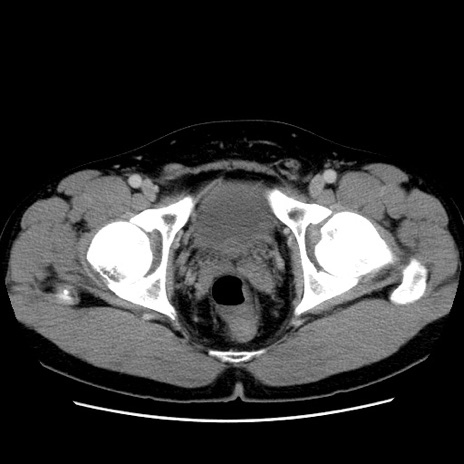

症例4(横断像)

【症例】30歳代男性

【主訴】腹痛、嘔吐

【現病歴】昨晩から突然の腹痛あり、その後嘔吐、軟便も出現。腹痛が改善しないため救急搬送となる。2日前にしめ鯖の食事歴あり。

【身体所見】意識清明、苦悶様、BP 135/90mmHg、BT 35.7℃、腹部:平坦、やや硬、心窩部〜臍部に自発痛、圧痛あり、筋性防御+、反跳痛-

【データ】WBC 8100、CRP 0.57